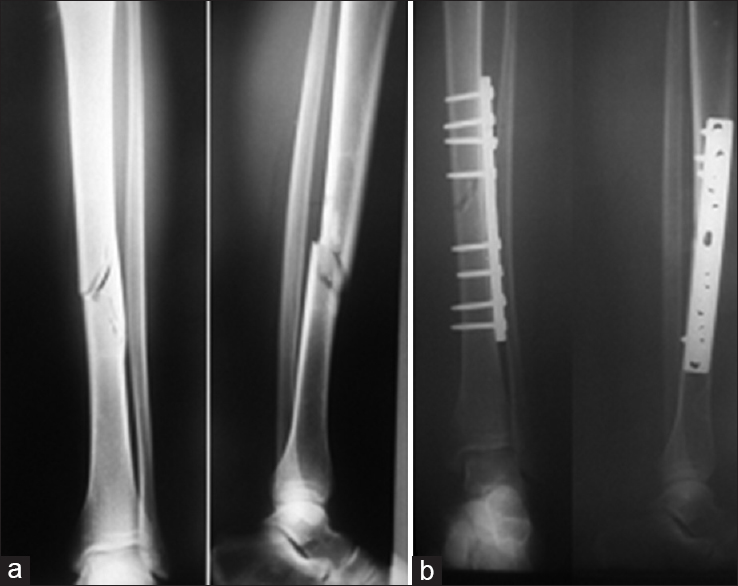

Upload Date: March 31, 2019 Full Size Image Dimensions: 738 × 586 Image Parent Post: Κατάγματα κάτω άκρου

8b.Εσωτερική οστεοσύνθεση κατάγματος διάφυσης κνήμης